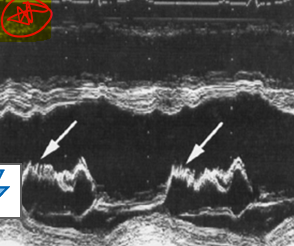

what is this?

diastolic fluttering of the AMVL caused by ao regurg

what murmur is associated with fluttering amvl due to ao regurg?

austin flint murmur

fluttering of anterior mitral valve leaflet can be caused by what pathology?

ao regurg